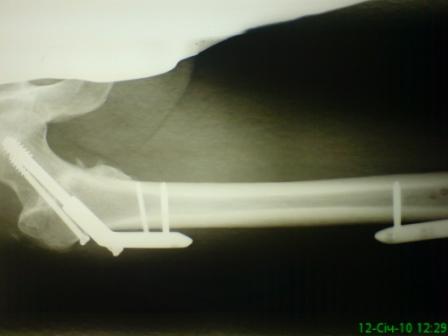

Больной, 30 лет, высокоэнергетическая травма 6 мес назад (базальный перелом шейки бедра + перелом дистального метаэпифиза бедра на той же ноге по типу 33-С2). Практически сразу же был произведен МОС шейки системой DHS (Synthes), через две недели - МОС дист.отдела бедра системой LISS (Synthes)плюс костная пластика с крыла подзвдошной кости.

На сегодняшний день наступил перелом пластины, укорочение бедра 2 см. Перелом шейки клинически и рентгенологически сросся. Больной астеничен, немного анемичен. Рентгенограммы прилагаются.